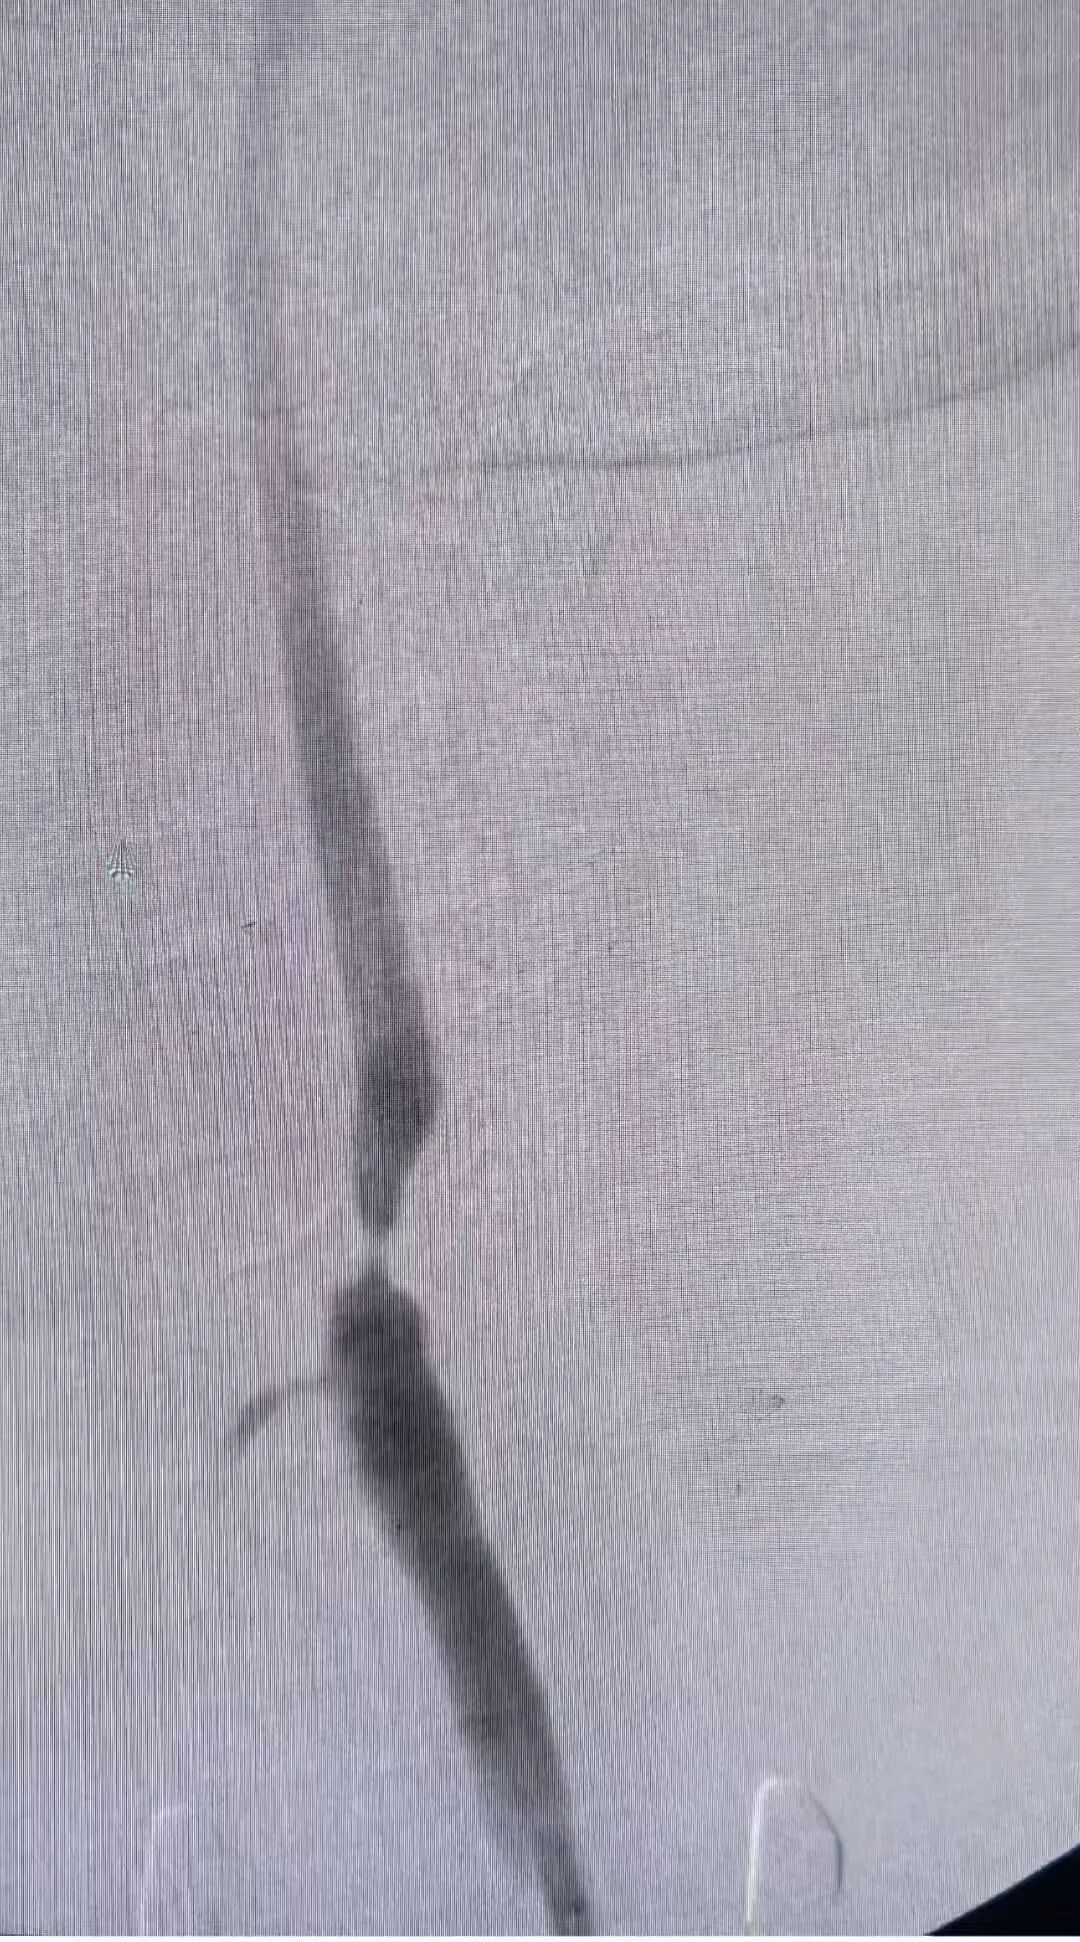

术前及术后造影图像:

本次手术由我院心脏血管外科核心团队主导,术前联合麻醉科、影像科等多学科进行全面评估,制定个性化手术方案;由兴安盟人民医院特聘教授刘鹏、兴安盟人民医院副院长周智勇主刀,术中团队密切配合,精准操作每一步,历时1.5小时顺利完成,术后患者生命体征平稳,无并发症发生,目前已顺利康复。